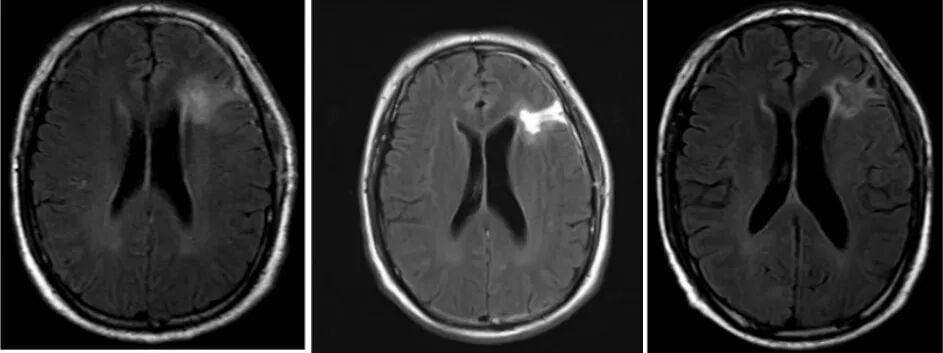

2021年8月,患者接受了左额颞岛叶胶质瘤切除术,术后病理证实为胶质母细胞瘤(WHO 4级)。随后,患者接受了标准的术后辅助治疗:从2021年9月至11月,进行了同步放化疗(放疗DT=60Gy/30f,同步口服替莫唑胺),之后继续替莫唑胺辅助化疗。初期治疗效果显著,复查MRI显示病变范围缩小。

图2. 标准治疗期间的影像学变化